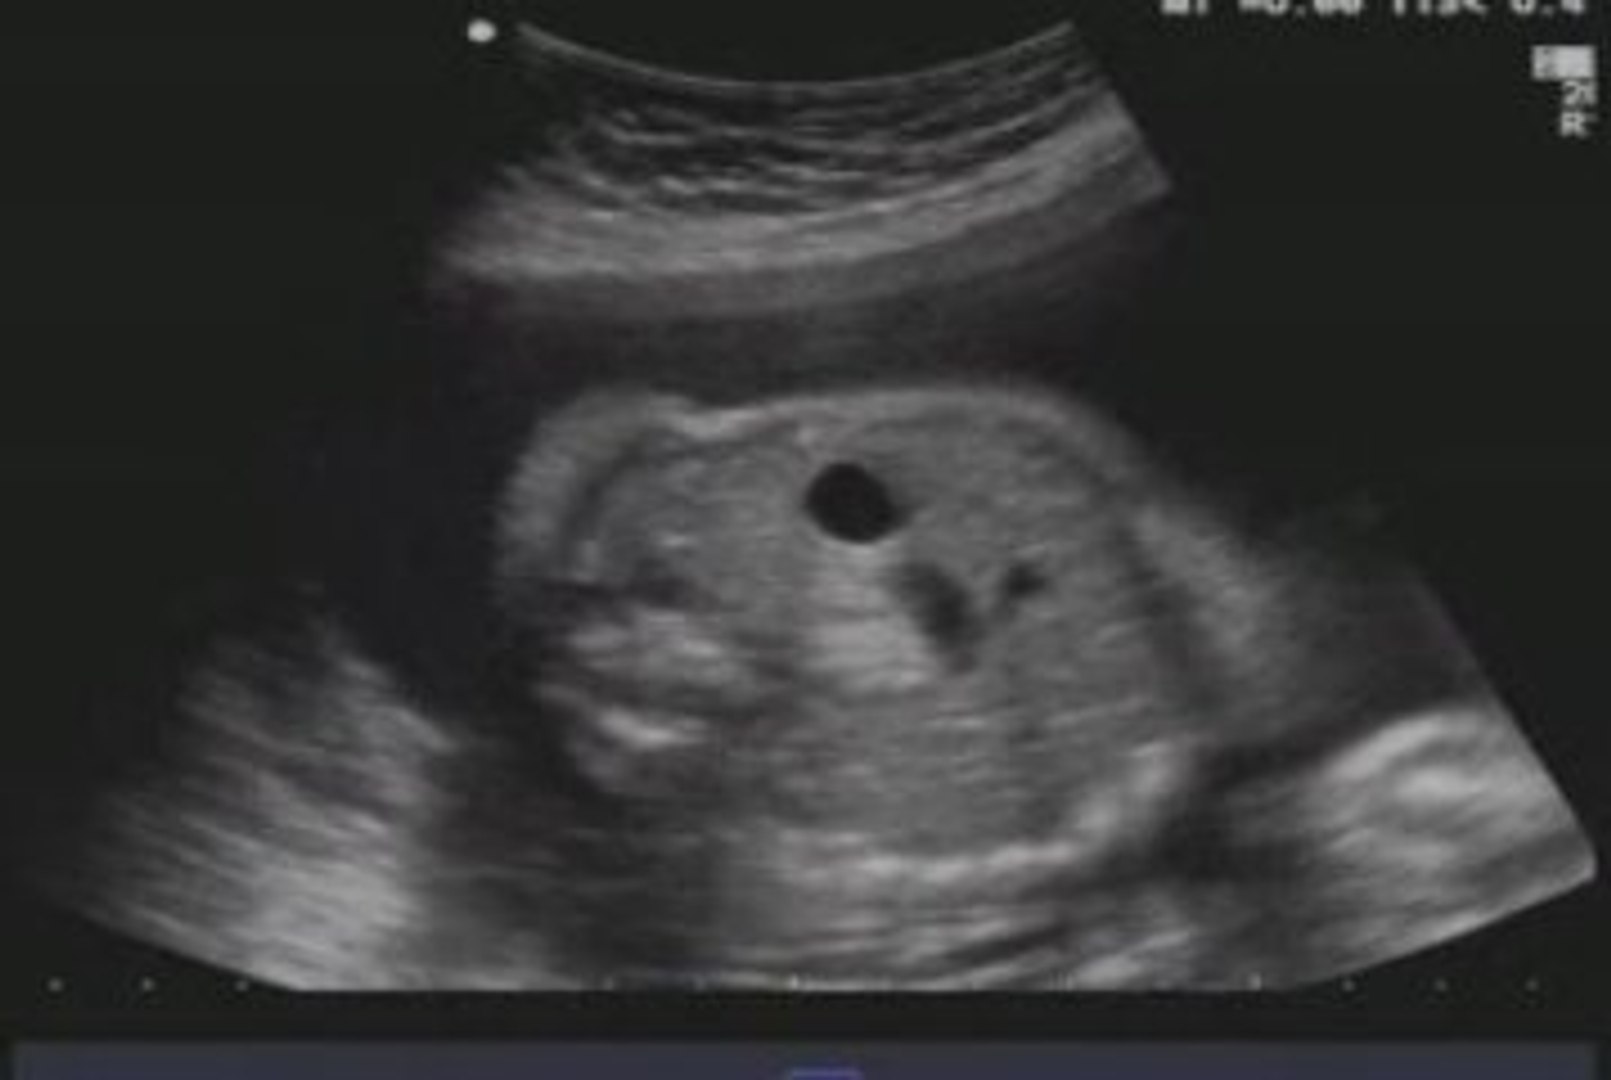

Duodenal atresia is the congenital absence or complete closure of a portion of the lumen of the duodenum It causes increased levels of amniotic fluid during pregnancy (polyhydramnios) and intestinal obstruction in newborn babies. Duodenal atresia is due to the failure of canalization of the embryonic duodenum This failure may be related to an ischemic event or genetic factors Duodenal atresia, unlike other intestinal atresias, is commonly associated with other congenital anomalies such as Down syndrome, which is present in 25 to 40% of cases. Duodenal atresia is an embryopathy of the cranial intestine that leads to a complete absence of the duodenal lumen.

Duodenal atresia (DWAHdenal ahTREEzha) is a condition that occurs when a portion of the duodenum doesn’t form This condition results in a blockage (atresia) that stops food or fluid from leaving the baby’s stomach (Figure 2). Duodenal atresia is a problem with the development of a baby's duodenum, the part of the small intestine that connects the stomach to the rest of the intestine Instead of an open tube into the intestine, a baby with duodenal atresia has a blockage or gap between the duodenum and intestine. Un atresia duodenale è una chiusura o l'assenza della apertura del primo tratto dell'intestino tenue collegandolo allo stomaco e, se non trattata, può essere mortale Associato con sindrome di Down, una ostruzione duodenale è anche legato a casi di polidramnios, che è un accumulo di liquido amniotico nel sacco amniotico durante la gravidanza.

If duodenal atresia is diagnosed early, electrolyte and fluid balance should be normal If the diagnosis is delayed at all, laboratory assessment of electrolyte and fluid status is imperative for. Key Words Duodenal atresia SOMMARIO L’atresia dudenale ha un’incidenza di circa nati vivi L’outcome dei pazienti con ostruzione duodenale, in termini di tasso di mortalità, risulta migliorato nelle ultime decadi, soprattutto grazie al miglioramento della qualità della diagnosi prenatale e dell’assistenza neonatale. Duodenal atresia is associated with prematurity and low birth weight Duodenal atresia is prenatally detected in 32%57% of patients, and fetal ultrasound may show polyhydramnios Patients present with vomiting, which can be bilious or nonbilious The abdominal xray shows a “double bubble”.

Duodenale atresia is meestal dodelijk als de behandeling niet binnen de eerste paar dagen van het leven wordt toegediend Een team van ervaren chirurgen kan proberen om de toestand te verhelpen door de darm met de hand te openen en te verwijderen van weefsel dat wordt veroorzaakt door de blokkade. Duodenal atresia is the congenital absence or complete closure of a portion of the lumen of the duodenumIt causes increased levels of amniotic fluid during pregnancy (polyhydramnios) and intestinal obstruction in newborn babiesRadiography shows a distended stomach and distended duodenum, which are separated by the pyloric valve, a finding described as the doublebubble sign. Over 35,000 people have already used this information to overcome their duodenal ulcer problems with a success rate of over 98%.